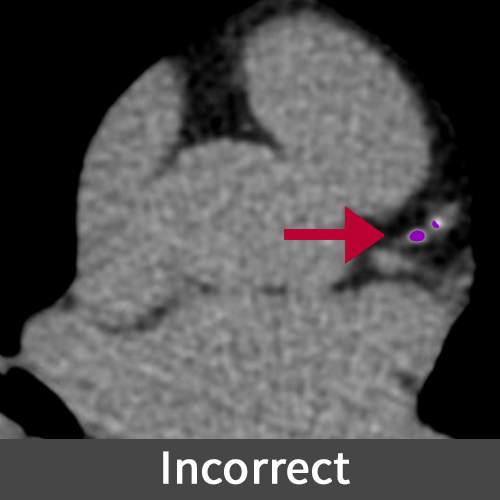

Calcium Score

A calcium score, determined through a cardiac CT scan, quantifies the amount of calcium in the coronary arteries, serving as an indicator of coronary artery disease and helping assess the risk of future heart problems. Higher scores indicate a greater plaque burden and an increased risk of heart disease, aiding doctors in treatment decision-making.

Missing calcified regions in a report can lead to an underestimation of coronary artery disease severity, potentially delaying necessary treatments and increasing the risk of heart-related complications for the patient.

Figure E (Right): Incorrect and correct markings of the calcium used for the Calcium Score evaluation.